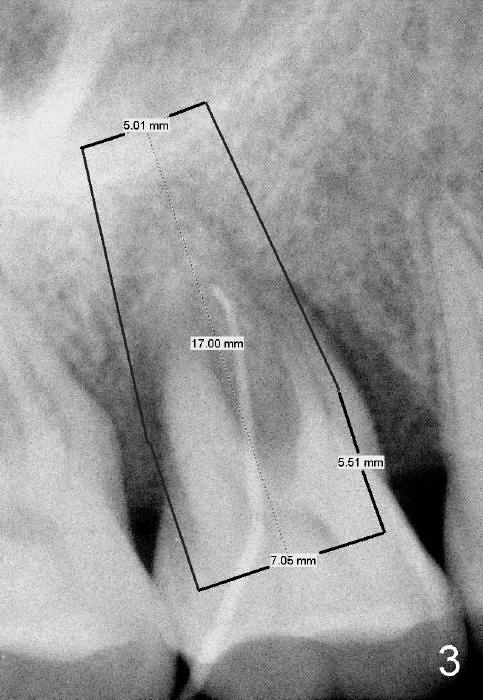

The tooth #3 has severe periodontitis with probably endodontic lesion (Fig.1,2). The patient is a 43-year-old man with apprehension of dentistry. An acute infection causes pain and tooth shift (Fig.4,5). A 7x17 mm immediate implant is planned (Fig.3). The palatal socket is shallow (Fig.6 P), corresponding to severe recessive palatal root (Fig.5 P). The osteotomy is created mainly in the buccal socket (Fig.6 B), exactly in the lingual slope of the septum. Initially osteotomes are used, followed by tap placement (Fig.7 T (4.5x20 mm at the depth of 17 mm). When the implant is placed as planned (Fig.8 I), there is more vertical contact (Fig.8 red line) than that associated with the tap (Fig.7 red line). The corresponding insertion torque is between 50 and 60 Ncm. There is only one small gap buccally, which is filled with bone graft (Fig.9 <). After the insertion of a short abutments with vertical slots (Fig.9,10 A), perio dressing is used to cover the wound. The palatal socket is expected to heal uneventfully (Fig.10 P). In fact, it does in 7 days (Fig.12 P); the bone graft in the mesiobuccal aspect is healing and stabilized (Fig.11 <). By two weeks postop, the mesiobuccal socket has healed (Fig.13 <). With removal of a diseased tooth, our body has amazing power to heal.